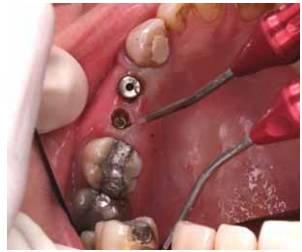

Figure 1 depicts the use of a diode laser in an implant recovery procedure.

The specific wavelengths of light emitted by the diode laser are absorbed by certain tissues. These lasers often utilize a 200-micron fiber, comparable to the width of a 20K file. Diode lasers can be employed as an alternative to a scalpel in the second stage of surgery.